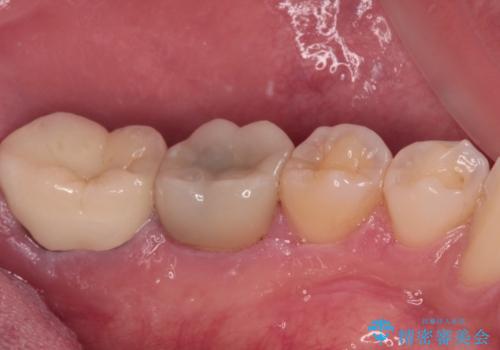

- 間もなく海外赴任という状況で奥歯のクラウンが割れてしまったとのことで来院された患者様です。

下顎の1番奥の歯であり、歯肉に覆われている部分が大きいためセラミックの十分な厚みが取れない状態でした。

強化セラミックを用いたオールセラミッククラウンにて補綴治療を行うこととしました。

十分な土台の高さを確保できない状態であったので、維持力のある土台の形態に整えることで、極力長持ちする治療を心がけました。